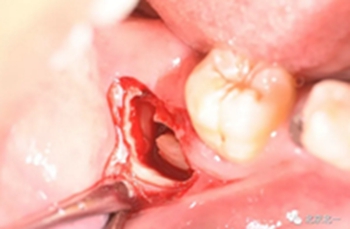

去骨:原則暴露最大周徑線即可, 盡可能少去骨, 微創(chuàng)拔除。

截冠:有絲分裂至關(guān)重要。 保證微創(chuàng)下拔除智齒。